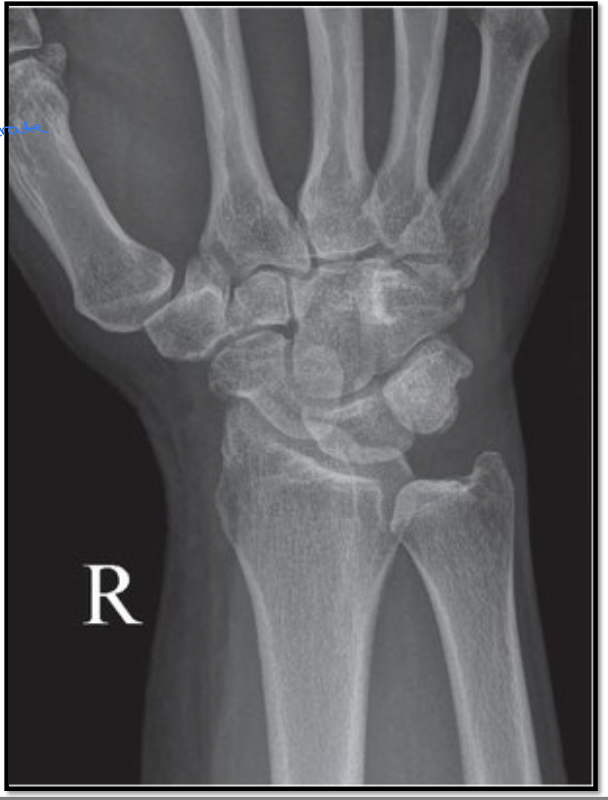

1

PA wrist criteria

A

• Styloid processes are at the extreme edges

• CMC joint spaces are open (MC’s do not obscure carpal bones)

• Scapholunate joint space is open

• Ulnar border of pisiform is positioned outside of ulnar border of the

triquetrum

• Minimal overlap of distal radius

• Radioulnar joint is open

• Posterior surface of wrist and hand

parallel to IR